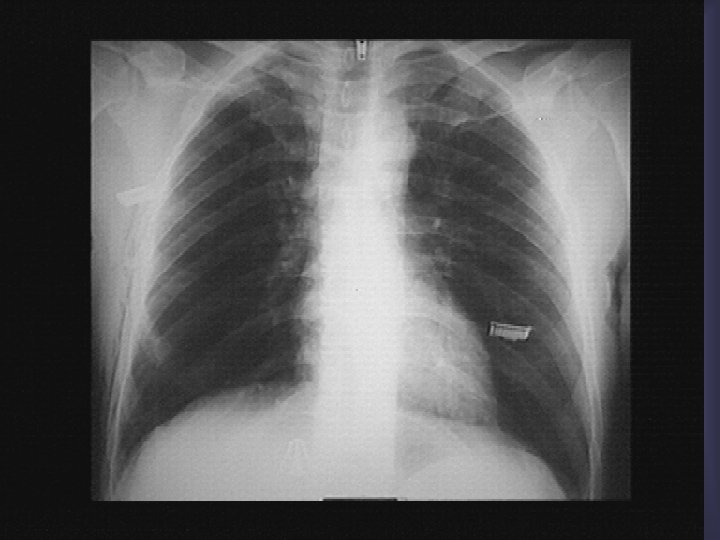

PNO bilatéral sur pneumocystose